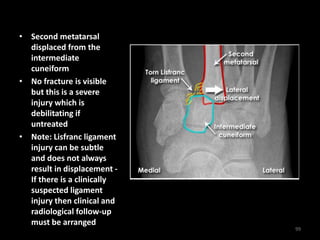

• Second metatarsal

displaced from the

intermediate

cuneiform

• No fracture is visible

but this is a severe

injury which is

debilitating if

untreated

• Note: Lisfranc ligament

injury can be subtle

and does not always

result in displacement -

If there is a clinically

suspected ligament

injury then clinical and

radiological follow-up

must be arranged

99